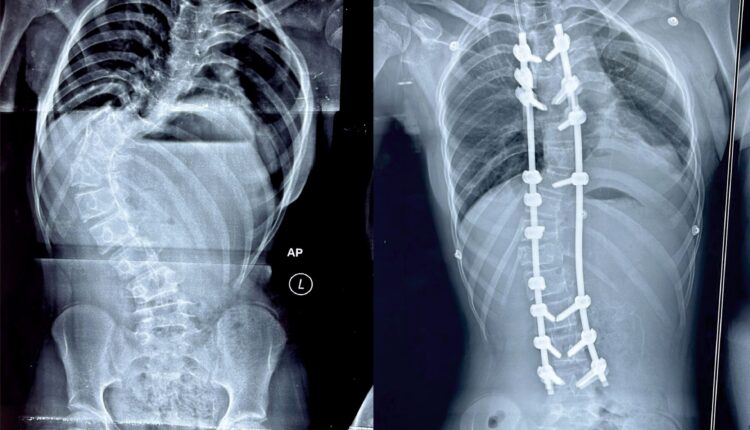

ଭୁବନେଶ୍ୱର: ମେରୁଦଣ୍ଡ ବଙ୍କା ହୋଇଯାଇଥିବା ଜନୈକା ବାଳିକାଙ୍କଠାରେ ସଫଳ ଅସ୍ତ୍ରୋପଚାର ଏହାକୁ ସଳଖ କରି ପାରିଛନ୍ତି କିମ୍‍ସର ଡାକ୍ତର। ସ୍କୋଲିଓସିସ୍ ନାମକ ଗୁରୁତର ମେରୁଦଣ୍ଡ ସମସ୍ୟା ସହ ଦୀର୍ଘ ଦିନ ଧରି ସଂଘର୍ଷ କରୁଥିବା ଏହି ବାଳିକାଙ୍କ ଅଭିଭାବକ ବହୁ ଖ୍ୟାତି ସମ୍ପନ୍ନ ଡାକ୍ତରଖାନାରୁ ନିରାଶ ହୋଇ ଶେଷରେ କିମ୍‍ସ ଡାକ୍ତରଙ୍କ ସହ ପରାମର୍ଶ କରିଥିଲେ। ଅସ୍ଥିଶଲ୍ୟ ବିଶେଷଜ୍ଞ ତଥା ସ୍ପାଇନ୍ ସର୍ଜନ ଡା ଜିତେନ୍ଦ୍ର କୁମାର ରାଉତ ରୋଗୀଙ୍କୁ ଦେଖିବା ପରେ ଏହା ‘ଇଡିଓପାଥିକ ସ୍କୋଲିଓସିସ୍‌’ ନାମକ ଏକ ପ୍ରକାର ମେରୁଦଣ୍ଡ ସମସ୍ୟା ବୋଲି ଜାଣି ତୁରନ୍ତ ଅସ୍ତ୍ରୋପଚାର ପାଇଁ ପରାମର୍ଶ ଦେଇଥିଲେ। ନିଶ୍ଚେତକ ବିଭାଗର ଡା ସଞ୍ଜୀବ ଗିରି ଓ ରାଜ ମୋହନଙ୍କ ସହଯୋଗରେ ସ୍ପାଇନ୍ ସର୍ଜନ ଡା ରାଉତ ଏହି ଅସ୍ତ୍ରୋପଚାର କରିଥିଲେ। ବାଳିକାଙ୍କ ମେରୁଦଣ୍ଡ ଇଂରାଜୀ ଅକ୍ଷର ‘ଏସ୍‌’ ଆକୃତିର ହୋଇଯାଇଥିଲା, ଯାହା ଭବିଷ୍ୟତରେ ତାଙ୍କ ପାଇଁ ଆହୁରି ଅନେକ ସମସ୍ୟା ସୃଷ୍ଟି କରିଥାନ୍ତା ବୋଲି ଡା. ରାଉତ ପ୍ରକାଶ କରିଛନ୍ତି। କିମ୍‌ସରେ ଦକ୍ଷ ଡାକ୍ତର, ଉନ୍ନତ ଜ୍ଞାନକୈଶଳ ଓ ଯନ୍ତ୍ରାଂଶ ଉପଲବ୍‍ଧ ଯୋଗୁଁ ଏଭଳି ବିରଳ ମେରୁଦଣ୍ଡ ଅସ୍ତ୍ରୋପଚାର ସମ୍ଭବ ହୋଇପାରିଲା। ସେ ବର୍ତ୍ତମାନ ସମ୍ପୂର୍ଣ୍ଣ ସୁସ୍ଥ ହୋଇଛନ୍ତି। କିଛି ଦିନ ବିଶ୍ରାମ ପରେ ସେ ସ୍ୱାଭାବିକ ଜୀବନଯାପନ କରିପାରିବେ ବୋଲି ଡାକ୍ତର ରାଉତ କହିଛନ୍ତି। ସାଧାରଣତଃ ୧୦ରୁ ୧୫ ବର୍ଷ ବୟସ ମଧ୍ୟରେ ଏହି ରୋଗ ଦେଖାଦେଇପାରେ। ତୁରନ୍ତ ରୋଗର ଚିହ୍ନଟ ଓ ଉପଯୁକ୍ତ ସମୟରେ ଏହାର ଚିକିତ୍ସା କରାଗଲେ ଏହି ରୋଗର ଉପଶମ ହୋଇପାରିବ। ଏହା ରୋଗୀର ଆତ୍ମବିଶ୍ୱାସ ଏବଂ ଆତ୍ମସମ୍ମାନକୁ ପ୍ରଭାବିତ କରିପାରେ। ଏପରି ରୋଗୀ ଅନେକ ସମୟରେ ଥଟ୍ଟା ଏବଂ ଉପହାସର ପାତ୍ର ହୋଇଥାନ୍ତି। କମ୍ ବୟସରୁ ହିଁ ଏହାର ଚିକିତ୍ସା କରାଯିବା ଆବଶ୍ୟକ ନଚେତ ବୟସ ବଢ଼ିବା ସହିତ ଏହାର ଚିକତ୍ସା ମଧ୍ୟ ଅଧିକ ଜଟିଳ ହୋଇଯାଇଥାଏ ବୋଲି ଡା. ରାଉତ କହିଛନ୍ତି।

ସୂଚନାଯୋଗ୍ୟ, ପ୍ରଥମଥର ପାଇଁ ଓଡ଼ିଶାର ଏକ ଘରୋଇ ହସ୍ପିଟାଲରେ ଏଭଳି ଜଟିଳ ମେରୁଦଣ୍ଡ ଅସ୍ତ୍ରୋପଚାର କରାଯାଇପାରିଛି। ଏଭଳି ବିରଳ ଅସ୍ତ୍ରୋପଚାର କରି ‘କିମ୍‌ସ’ ରାଜ୍ୟର ଉନ୍ନତ ସ୍ୱାସ୍ଥ୍ୟସେବା ପ୍ରଦାନକାରୀ ଅନୁଷ୍ଠାନ ଭାବେ ପ୍ରମାଣିତ କରିପାରିଛି। ଏହି ମେରୁଦଣ୍ଡ ଅସ୍ତ୍ରୋପଚାର ସାଧାରଣତଃ ୭-୮ ଘଣ୍ଟା ସମୟ ଲାଗିଥାଏ, କିନ୍ତୁ କିମ୍‌ସର ସ୍ପାଇନ ସର୍ଜନ ତଥା ଓଡ଼ିଶା ସ୍ପାଇନ ସଂଘର ସମ୍ପାଦକ ଡା. ରାଉତ ଏବଂ ତାଙ୍କ ଡାକ୍ତରୀ ଦଳ ମାତ୍ର ୪ ଘଣ୍ଟାରେ ଏହି ସଫଳ ଅସ୍ତ୍ରୋପଚାର କରିପାରିଥିଲେ। ଏଭଳି ବିରଳ ଅସ୍ତ୍ରୋପଚାର ପାଇଁ କିଟ୍‍, କିସ୍‍ ଓ କିମ୍‍ସ ପ୍ରତିଷ୍ଠାତା ଅଚ୍ୟୁତ ସାମନ୍ତ ଡା. ରାଉତ ଓ ତାଙ୍କ ଡାକ୍ତରୀ ଦଳକୁ ଧନ୍ୟବାଦ ଜଣାଇବା ସହ ବାଳିକାର ଆଶୁ ଆରୋଗ୍ୟ କାମନା କରିଛନ୍ତି। ବିଜୁ ସ୍ୱାସ୍ଥ୍ୟ କଲ୍ୟାଣ ଯୋଜନା (ବିଏସ୍‌କେୱାଇ) ଅଧୀନରେ ରୋଗୀଙ୍କର ମାଗଣା ଚିକିତ୍ସା କରାଯାଇଥିଲା।